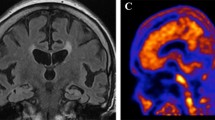

The patient underwent a florbetaben-PET (FBB-PET) scan which showed extensive FBB retention that was greater in parietotemporal, frontal and posterior cingulate/precuneus cortex and less pronounced in the occipital cortex. Basal ganglia were also slightly affected (Fig. 3).

Aβ and tau imaging with FBB (top) and THK-5351 (bottom) of our 59 year old patient with Alzheimer’s disease. FBB and THK-5351 binding patterns demonstrate the different distributions of Aβ and tau deposits in the brain of our Alzheimer’s disease patient. FBB-PET scan revealed a massive global amyloid load with a pronounced FBB retention in parietotemporal, frontal and posterior cingulate/precuneal cortices. In contrast THK-5351 retention was markedly elevated in the hippocampus, whereas onlya slightly increased THK-5351 retention was observed in parietotemporal cortical areas

The tau-PET scan with THK-5351 on the other hand showed high tracer retention in both hippocampi as well as moderately increased tracer retention in parietotemporal cortical areas. There was no elevated tracer retention in other cortical areas (Fig. 3).

Amyloid-PET showed a characteristic increase of tracer uptake in cortical regions known to have a high amount of amyloid burden in AD, i.e. frontal, parietal and lateral temporal cortex (Fig. 3). DLB patients can show a similar pattern yet with lower amount of Aβ ligand binding compared with AD patients [43]. FTD patients on the other hand display low cortical tracer retention such that amyloid PET has shown high accuracy in discriminating AD from FTD [44, 45]. Variable degrees of diffuse β-amyloid can be detected in about 47 % of autopsy confirmed CTE cases [46]. Amyloid-PET may therefore differentiate between CTE and AD by identifying different amyloid-deposition patterns. Further studies are needed to determine the topography of β-amyloid depositions in CTE. Showing a high amount of tracer uptake in parietotemporal, frontal and posterior cingulate/precuneus cortex, FBB-PET was suggestive for AD in our case. Recent phase III studies in which the in-vivo uptake of 18-F-labelled amyloid tracers was compared to post-mortem amyloid load showed a sensitivity and specificity of 88 to 92 %, and 88 to 100 % respectively for the detection of amyloid deposits in AD patients [47–49]. As amyloid deposition probably represents a very early event in the course of the disease that occurs years before onset of dementia symptoms, amyloid-PET may allow early and even presymptomatic diagnosis [4].

Increased tau-tracer retention could be detected in parietotemporal cortical areas, especially in the hippocampus (Fig. 3). In contrast to amyloid-PET the sensitivity and specificity of tau-PET imaging have yet to be determined. Post-mortem studies have shown that the amount of tau deposition is highly related to the severity of dementia [50]. In addition to aiding in the early and differential diagnosis of Alzheimer’s disease tau-PET may therefore serve as a marker of disease progression. Recently, first experiences with tau-PET in DLB were reported [51]. Tau deposition is elevated in some cases of DLB, especially in the inferior temporal region. Tau-PET scans may be positive in some variants of FTD. A first case report of a P301L MAPT mutation carrier showing elevated tau tracer uptake in frontal, anterior temporal and parietal cortex as well as in basal ganglia has been published [30]. Hitherto a single case report of a patient with a clinical diagnosis of CTE who underwent tau-PET imaging has been published [52]. Increased tracer uptake could be detected in globus pallidus, putamen, hippocampus and substantia nigra. Because of increased tracer retention in basal ganglia the detected distribution of tracer retention seemed more suggestive of progressive supranuclear palsy. However the patient did not manifest the typical clinical symptoms of progressive supranuclear palsy. In summary tau-PET also supported a diagnosis of AD in our case.